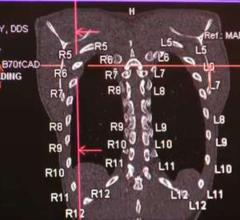

Treatment planning systems are at the heart of radiation therapy (RT) and the key to improved patient outcomes. Once image datasets are loaded and the tumors are identified, the systems develop a complex plan for each beam line route for how the therapy system will deliver radiation.